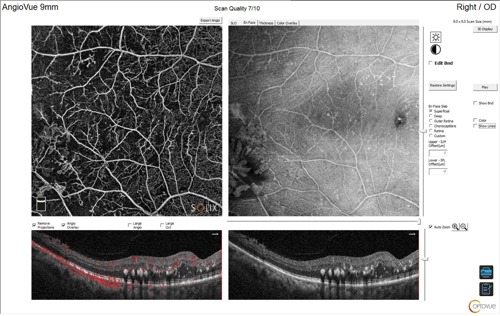

Optical coherence tomography (OCT) and OCT angiography (OCT-A) were performed using the Optovue Solix Spectral Domain OCT system (Visionix) to assess for the presence of neovascularization and macular edema. Due to the equatorial location of the anomalous vasculature, 9x9 mm and 12x12 mm OCT-A were selected.

The utilization of OCT-A was instrumental in confirming the diagnosis of proliferative diabetic and sickle cell retinopathy and identifying associated macular edema. Employing advanced imaging technologies enhances diagnostic accuracy and supports improved clinical decision-making.